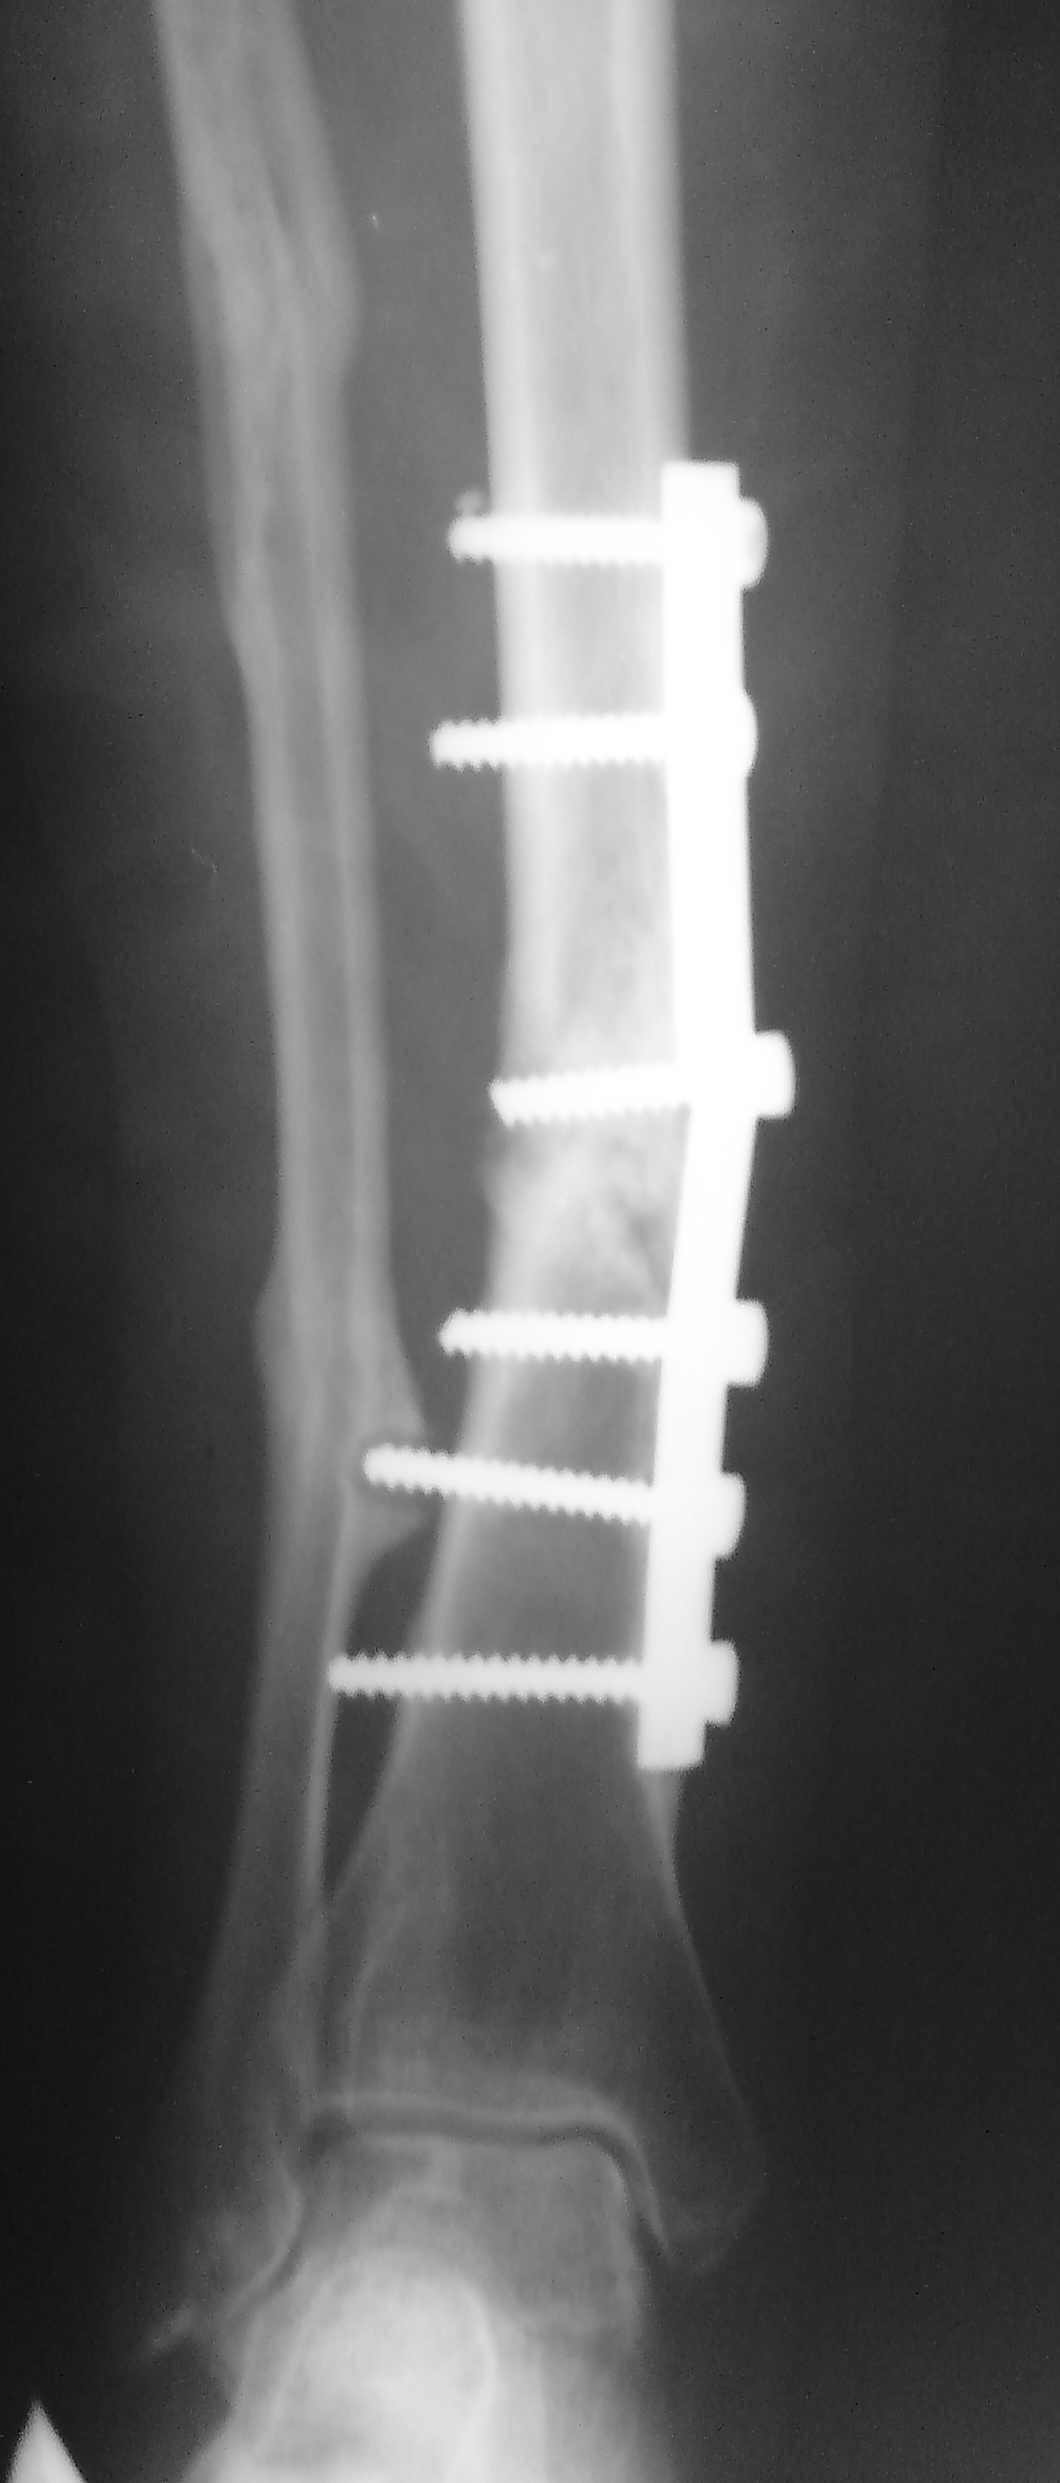

[Ortho] Ложный сустав н/3 б/берцовой кости

Здравствуйте уважаемые коллеги.В нашу клинику обратилась б-ая 48 лет,

Здравствуйте уважаемые коллеги.В нашу клинику обратилась б-ая 48 лет,перелом обеих костей

голени в 2006 ,ВЧОС по Илизарову;операция по поводу ложного сустава 2008.Хотелось бы узнать

Ваше мнение по тактике дальнейшего лечения